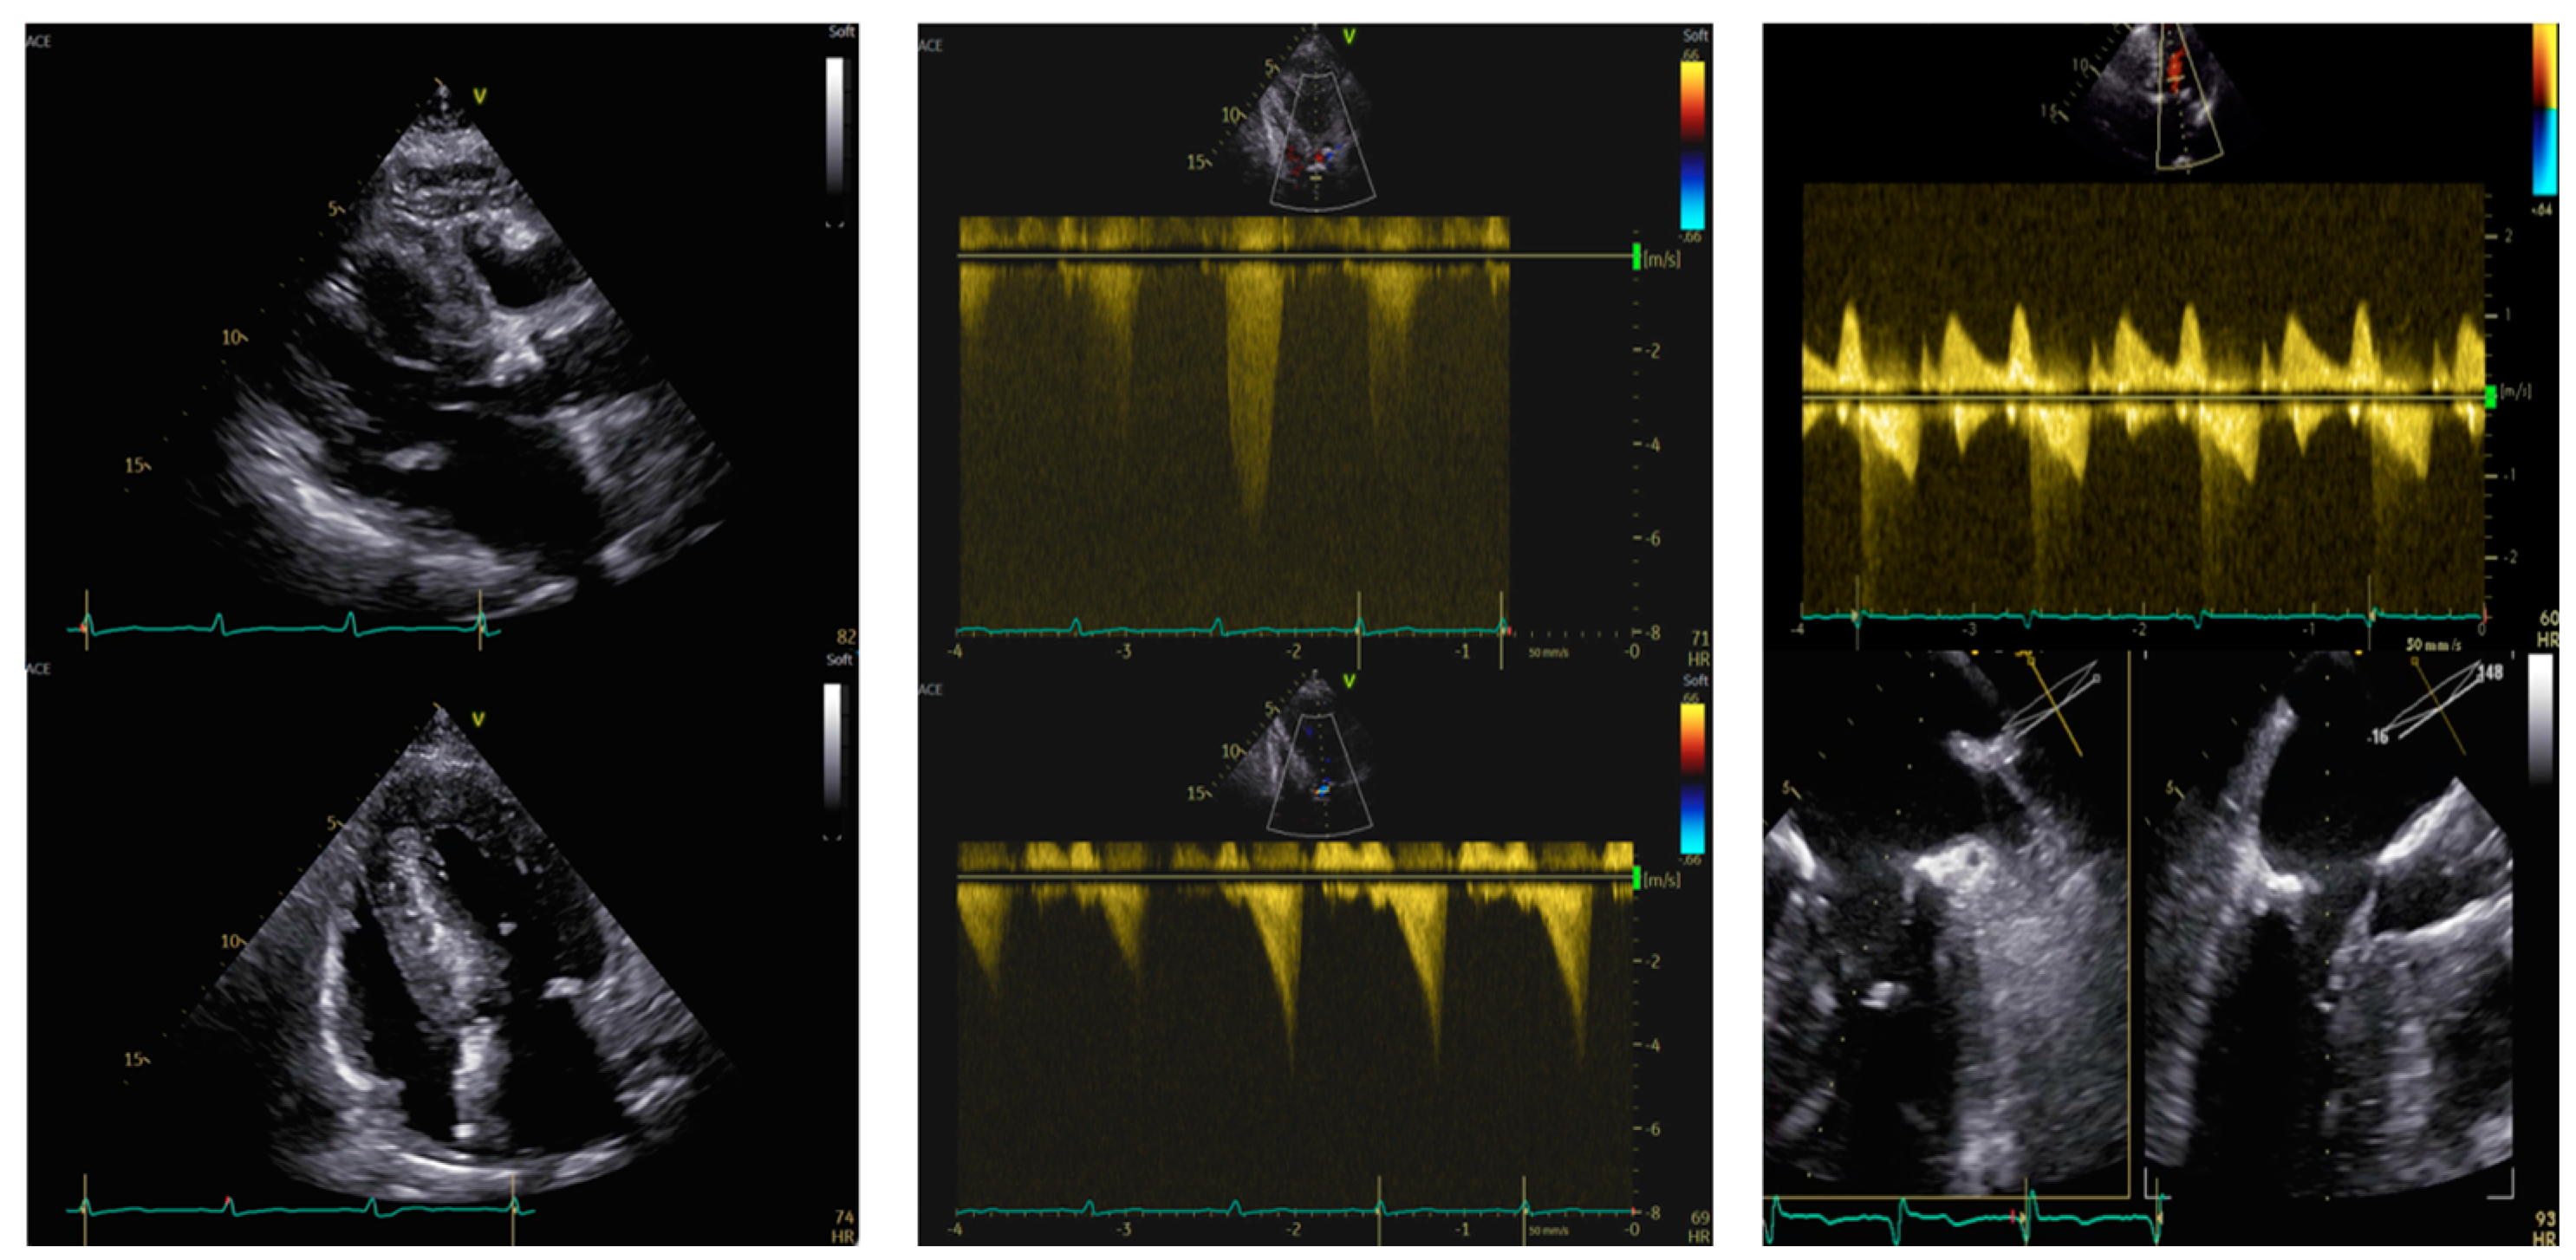

An 87-year-old woman with known severe AS was admitted for worsening dyspnea and fatigue upon mild exertion. Her medical history included hypertension, dyslipidemia, and a previous carotid endarterectomy meanwhile, her home medical therapy included antiplatelet agents, beta-blockers, statins, and diuretics. After a Heart Team discussion, she was proposed for TAVI. The pre-procedural coronary angiography showed patent coronary arteries. The Society of Thoracic Surgeons Score (STS score) Operative Mortality was 5.58%, Morbidity & Mortality was 13.3%, and EUROscore II was 7.02%. The pre-procedural transthoracic echocardiogram (TTE) revealed a marked HLV, with an interventricular septum (IVS) of 20 mm and normal ejection fraction (EF = 58%) with no regional wall motion abnormalities. The TTE also showed a paradoxical low-flow, low-gradient type [maximum gradient 53 mmHg, mean gradient 28 mmHg, Vmax 3.6 m/s, stroke volume index (SVi) 18 mL/m2], with possible underestimation of gradients due to small left ventricle size. LVOT Velocity Time Integral (VTI) was not assessable due to dynamic LVOT obstruction (LVOTO) caused by systolic anterior motion (SAM) of the subvalvular mitral apparatus leading to a maximum gradient at rest up to 24 mmHg, and with a Valsalva maneuver up to 54 mmHg. There was also an associated mild mitral valve regurgitation (MVR).

Figure 1. Transthoracic and transesophageal echocardiography in an 87-year-old woman with paradoxical low-flow low-gradient aortic stenosis. Left panel. PLAX view (upper) and 4-chamber view (lower). IVS telediastolic diameter = 20 mm, LVEDVi = 31 mL/m2. Central panel. Aortic valve peak velocity of 3.6 m/s (upper) with a mean gradient of 28 mmHg and a dynamic LVOT gradient (lower) of 54 mmHg after the Valsalva maneuver. Right panel after TAVI. SAM of the anterior mitral leaflet (upper, red arrow) by TEE causing severe mitral regurgitation. IVS: interventricular septum. LVEDVi: left ventricular end-diastolic volume indexed. LVOT: left ventricular outflow tract. SAM: systolic anterior motion.

The patient underwent TAVI with a 26 mm Evolut Pro+ bioprosthesis implantation. Upon valve deployment, the patient experienced marked hypotension (BP 60/40 mmHg). Mechanical complications such as pericardial effusion and vascular complications were ruled out. Due to severe desaturation, the patient was intubated and a temporary pacemaker was placed due to the onset of a complete atrioventricular block. Then the patient developed ventricular fibrillation, which was defibrillated with one effective DC shock. Post-procedural ventriculography showed normal left ventricular systolic function, a trans-prosthetic gradient of 20 mmHg, and the emergence of severe MVR. Post-procedural coronary angiography showed no coronary embolism in coronary arteries and no coronary ostia obstruction by the prosthesis. Aminergic support with norepinephrine, epinephrine, and dobutamine was required. The subsequent transesophageal echocardiography (TEE) confirmed the proper position of the aortic valve prosthesis, with mild paravalvular regurgitation. Significant acceleration in the LVOT (Vmax 4 m/s) was noted due to SAM of the anterior mitral leaflet (AML), with severe MVR. In the following days, aminergic support was gradually reduced. However, despite numerous attempts and no neurological complications, extubation was not possible due to concomitant acute pulmonary edema and sepsis. Percutaneous correction of the mitral defect was considered but not performed due to concurrent sepsis, patient fragility, and high risk of futility. The patient died a few days later.